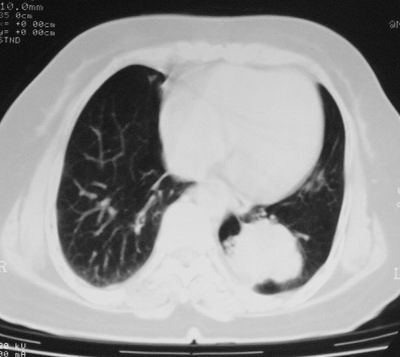

患者,女,64岁,4年前左腮腺"多形性"腺瘤手术治疗史.现复查胸部ct见左下肺块状影,该影与原左腮腺手术是否有联系?

本次复查胸部ct

左下肺软组织块影,有分叶、毛刺、空泡及胸膜牵拉征,左下肺周围性肺癌。

左肺下叶周围型肺癌,支持!(软组织肿块+分叶+毛刺+空泡+胸膜凹陷征)

左下肺软组织密度影,可见分叶,边缘可见毛刺征,胸膜增厚,强烈要求左下肺周围型肺癌

左下肺后基底段实性肿块,周围有毛刺,病变周围有肺气肿,与降主动脉间有条带状影相连,病灶4年前查体发现,纵隔内未见肿大淋巴结。考虑.肺隔离症,建议增强扫描与周围型肺癌鉴别。